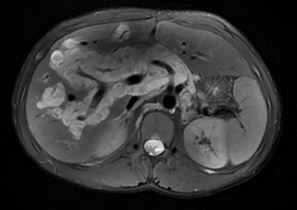

| 增强CT:图A、B,肝门区、胰头周围、肝内门静脉旁弥漫不规则斑片状、条片状低密度影,局部延伸至下腔静脉旁。PET-CT: 图C、D,肝内门静脉分支及主干旁、肝门区、胰头上方见多发囊性低密度影,放射性摄取低 图 2 全腹增强CT对比PET-CT |

CT对评估淋巴管瘤体是否破裂以及评估与重要器官、大血管的走行具有重要价值。本病例肝囊性淋巴管瘤在CT上表现为呈多房状,界限清晰的多发低密度囊性病灶,囊内密度均匀;增强后囊壁轻度细线样强化,门脉期、延迟期强化明显。MRI示均匀T1WI低信号和T2WI明显高信号,囊性肿物沿组织间隙呈“爬行性生长”,强化后肝内可见纤维分隔样结构。鉴别诊断主要是肝海绵状血管瘤,肝囊肿,肝包虫病,肝转移瘤,先天性肝内胆管扩张症等疾病。